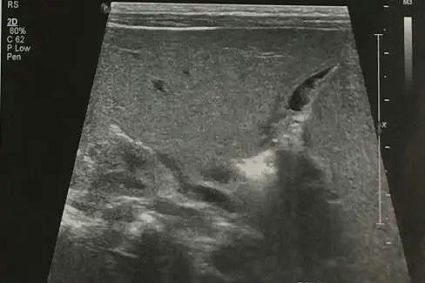

婴儿肝炎综合征(简称“婴肝”),因新生儿期或婴儿期病毒感染造成,为生理性黄疸消退后又出现黄疸,或持续性黄疸进行性加重,大便一般为黄色。超声表现为肝大、肝脏实质回声正常或增强,胆囊充盈良好或充盈较差,但胆囊形态大多流畅、自然(图1)。喂奶后1.5-2小时复查,充盈较好的胆囊会有不同程度的收缩,充盈差或萎瘪的胆囊会有少量的充盈。多数情况下,患儿的肝外胆道发育正常;重症肝炎时胆囊充盈差或不充盈,形态僵硬,喂奶前后无变化,这时与胆道闭锁鉴别困难,需要结合病史短期内(1-2周)复查,而且经过治疗后,黄疸程度不断减轻至恢复正常。

▲ 图1